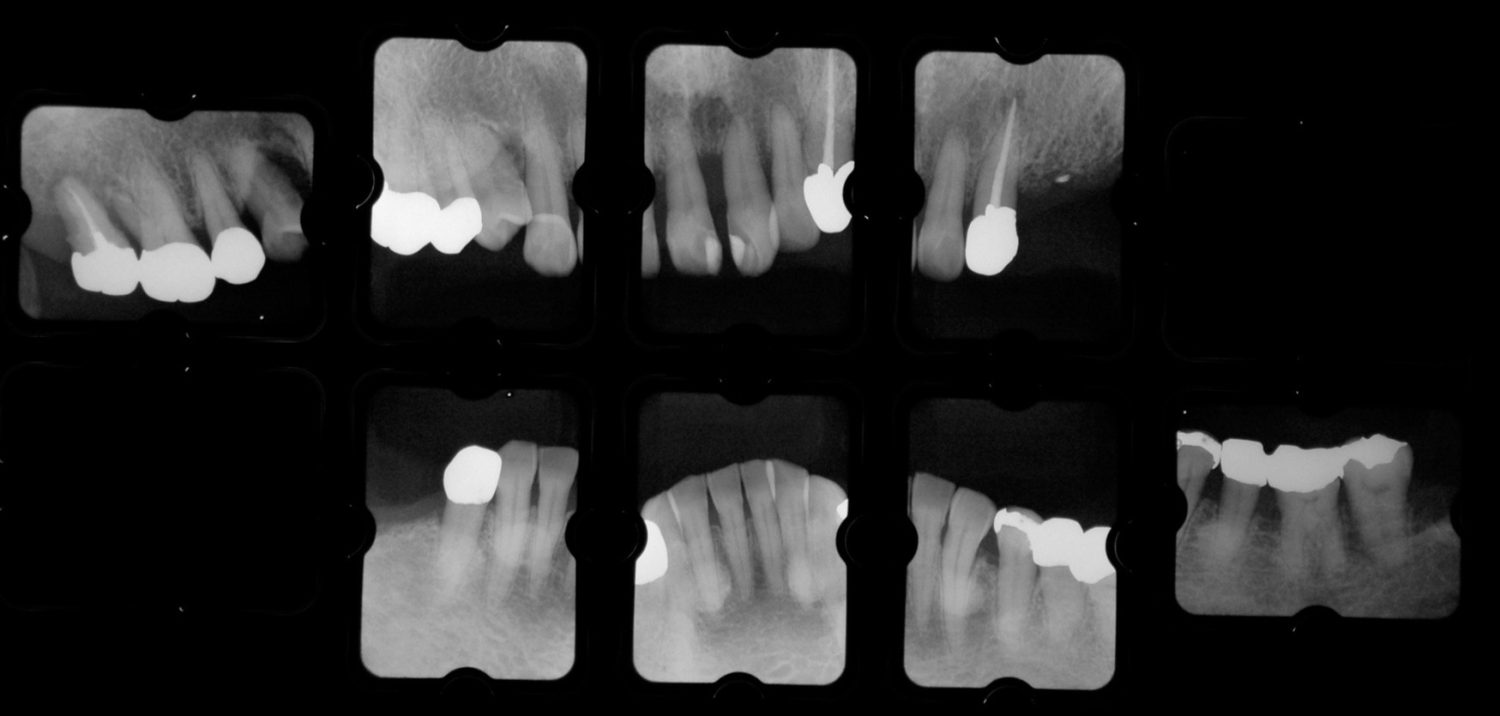

| 主訴 | 歯がグラグラで噛むことができない。インプラントをして欲しい。 |

| 治療内容 | 歯周病で骨の吸収が重度で保存不能なため抜歯、仮の入れ歯を作り、6ヶ月の抜歯窩の治療の後に、インプラントのCTによる診査診断を行い、下顎に6本インプラント埋入と同時に仮歯を入れる。その後、上顎は8本のインプラント埋入と同時に仮歯を入れる。左右上6はソケットリフトによる上顎洞拳上術を行う。その後免荷期間6ヶ月待ってセラミックを用いた上部構造作製、装着しメンテナンスに移行する。 |

| 治療費 | 9,000,000円(税込) |

| 治療期間 | 2年3ヶ月 |

| 治療回数 | 90回 |

| 想定されたリスク | 重度の歯周病により無歯顎になったため、プラークコントロール不良による、術後のインプラント周囲炎が懸念される。歯冠の部分はセラミックなため欠ける可能性がある。 |